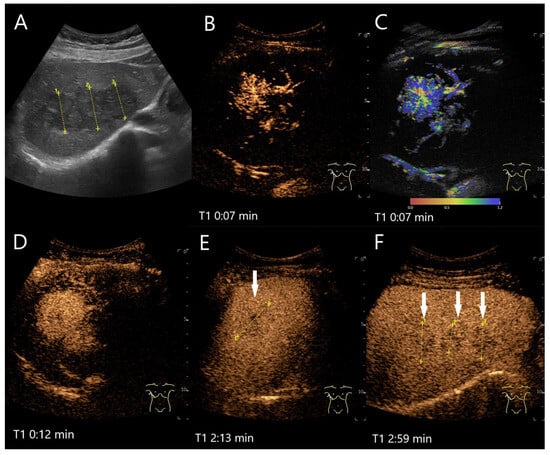

Figure 18.

Hepatic PEComa. In the left lobe of the liver there is a more than 5 cm large, oval, irregularly demarcated heterogeneous lesion (arrows) with several hyperechoic areas (A). In the AP of the CEUS (B) and in parametric imaging (C), the enhancement is initially lateral. The parametric imaging shows the chronological sequence of the arrival of the UCA in color. Then, the lesion is homogeneously hyperenhanced (D). In the PVP before 60 s, the hypoechoic parts show mild hypoenhancement (arrows) (E). The hyperechoic parts are isoenhanced or even slightly hyperenhanced. The hypoenhancement is slightly more pronounced at the beginning of the LP (F). This increases in the course of the LP (G) and is objectified in the time intensity curve (H). In the advanced LP the lesion shows a significant hypoenhancement (I). The washout with hypoenhancement was the reason for the US-guided biopsy, which resulted in a PEComa. This was confirmed by the histology of the surgical specimen.